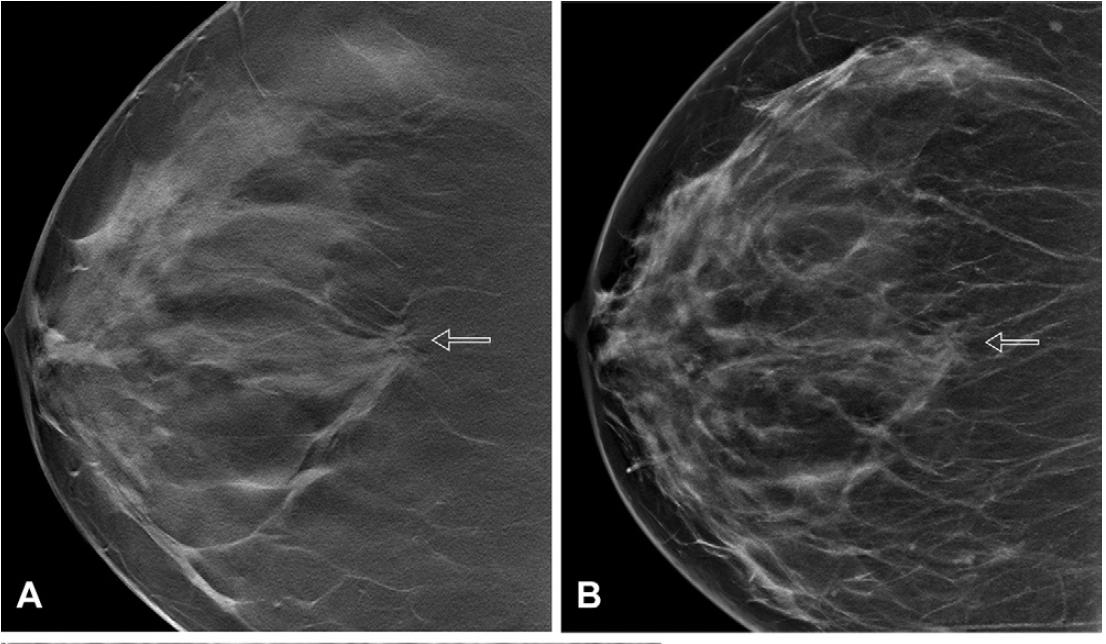

In a large study of nearly 100,000 women, researchers found that the combination of digital breast tomosynthesis (DBT) and synthesized mammography had more than triple the detection rate for invasive breast cancer in extremely dense breasts in comparison to digital mammography alone.

In a retrospective review involving over 2.2 million women with three consecutive biennial mammography screenings and no history of breast cancer, researchers noted that for premenopausal women with fatty breasts at baseline, increasing breast density at subsequent screenings led to significantly elevated hazard ratios ranging from 1.45 to 1.93 for the risk of breast cancer.